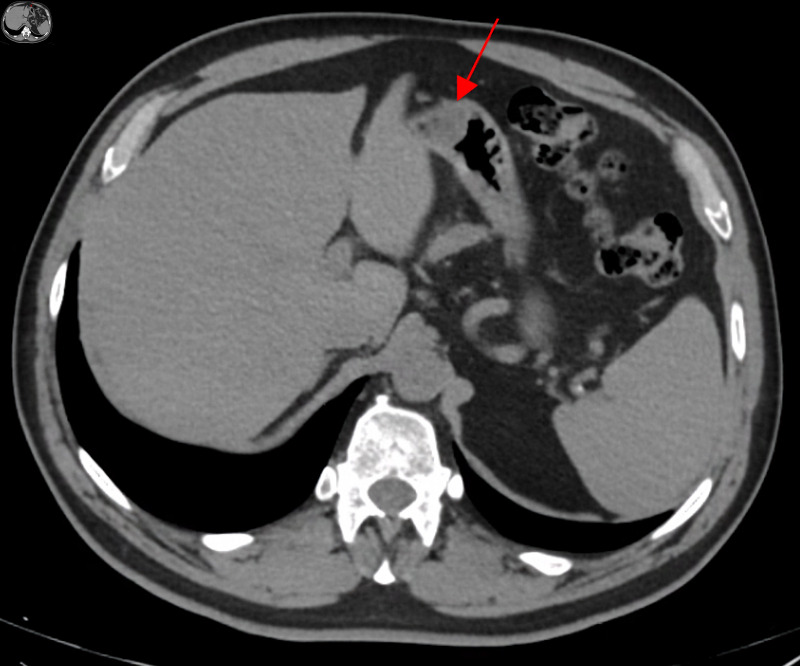

Gastric schwannomas and gastrointestinal stromal tumors (GISTs) are two types of mesenchymal tumors, which represent a group of rare tumors of the gastrointestinal tract. The differential diagnosis between these two tumors is difficult given their very similar appearance and clinical features. The authors present a case of a 63-year-old man with melena and epigastric pain. An upper digestive endoscopy was performed, revealing an ulcerated gastric subepithelial lesion suspected to be a GIST. Further imaging with a computed tomography (CT) scan revealed a well-defined hypodense solid nodular mass, with homogeneous enhancement, measuring 22 × 18 mm, on the anterior wall of the transition between the body and gastric antrum, situated within the submucosal layer. The patient subsequently underwent a laparoscopic atypical gastrectomy, which proceeded without complications. The pathological examination of the excised lesion confirmed it to be a gastric schwannoma, with complete excision. This case report illustrates a rare cause of gastrointestinal bleeding, that requires immediate action, and en bloc resection is usually curative. Given the excellent prognosis after complete resection, a correct diagnosis is essential.